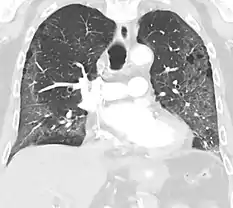

CT showing diffuse ground-glass opacities in periphery of both lungs in patient with COVID-19.

Ground-glass opacity is among the most common imaging findings in patients with confirmed COVID-19.[17][18] One systematic review found that among patients with COVID-19 and abnormal lung findings on CT, greater than 80% had GGOs, with greater than 50% having mixed GGOs and consolidation.[17] GGOs with mixed consolidation has most often been found in elderly populations.[19] Several studies have described a pattern among initial, intermediate, and hospital discharge imaging findings in the disease course of COVID-19. Most commonly, initial CT imaging reveals bilateral GGOs at the periphery of the lungs. During initial stages, this is most often found in the lower lobes, although involvement of the upper lobes and right middle lobe has also been reported early in the disease course.[17][19] This is in contrast to the two similar coronaviruses, SARS and MERS, which more commonly involve only one lung on initial imaging.[20][21] As the COVID-19 infection progresses, GGOs typically become more diffuse and often progress to consolidation.[12][19] This is sometimes accompanied by the development of a crazy paving pattern and interlobular septal thickening.[19] In many cases the most severe pulmonary CT abnormalities occurred within 2 weeks after symptoms began.[18] At this point, many individuals begin showing resolution of consolidation and GGOs as symptoms improve. However, some patients have worsening symptoms and imaging findings, with further increase in septal thickening, GGOs, and consolidation. These patients may develop lung "white-out" with progression to acute respiratory distress syndrome (ARDS) requiring treatment escalation.[18][22]

Preliminary reports have shown many patients have residual GGOs at time of discharge from the hospital. Due to the novelty of COVID-19, large studies investigating the long-term pulmonary CT changes have yet to be completed. However, long-term pulmonary changes have been seen in patients after recovery from SARS and MERS, suggesting the possibility of similar long-term complications in patients who have recovered from acute COVID-19 infection.[23]